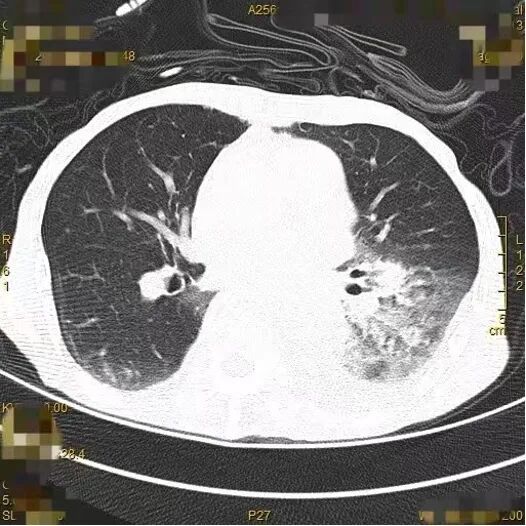

CT影像学检查(7月13日);CT影像学检查(7月16日)

图4-5 胸部CT结果

CT影像学检查(8月19日,较前明显好转)

图6胸部CT结果

对比7月13日、7月16日及8月19日的胸部CT影像(图4-6)可见,经规范抗感染治疗后,患者肺部病灶较前明显吸收好转。